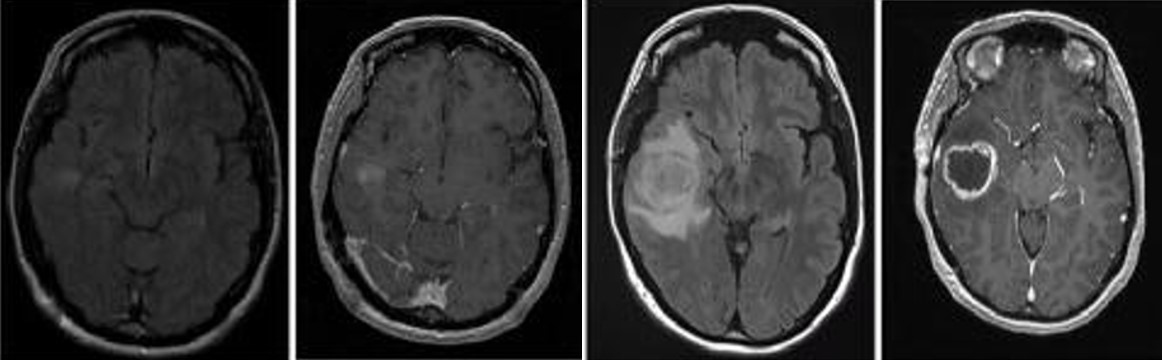

胶质母细胞瘤(Glioblastoma , GBM)是中枢神经系统中比较常见的神经上皮肿瘤,是恶性程度最高的原发性脑肿瘤也是最致命的实体瘤,被世界卫生组织归类为级胶质瘤。GBM 预后差,被诊断后的平均中位生存期为 14个月5年生存率为 5%。尽管目前在外科手术,放化疗等医学治疗手段取得了不错的进展,但在延长患者的生存期上仍未取得突破。因此,目前迫切需要筛选鉴定出有效的GBM生物标记物,探索GBM的治疗靶标并解析GBM的发病机理,GBM的早期诊断及预后评估提供新策略以延缓患者的生存期。

崔红娟教授团队就GBM标志物的筛查、鉴定以及如何管控EGFRGBM的表达开展了深入研究。首先, GBM患者组织的免疫组化病理检测以及生物信息学分析发现一种能够参与异染色质形成的H3组蛋白甲基化阅读器CBX3Chromobox 3)在GBM患者中异常高表达,并且与GBM的预后和恶性分级密切相关。功能检测表明了CBX3 在体外和体内显著促进 GBM 细胞的增殖、侵袭和肿瘤发生。从机制上来说,我们通过Ch-IPCo-IP等一系列生物技术实验证明了CBX3促进GBM 的恶性进展是EGFR 依赖性的,并且进一步揭示了GBM患者发病机理的一条全新的信号通路CBX3-PARK2/STUB1-EGFR。该研究不仅丰富了GBM表观遗传学的研究,也为该信号通路作为GBM潜在治疗靶点的可行性提供了坚实的依据。西南大学2020级博士研究生彭文为第一作者,崔红娟教授为该论文的通讯作者。该研究得到了重庆市自然科学基金和重庆市博士生科研创新项目的支持。